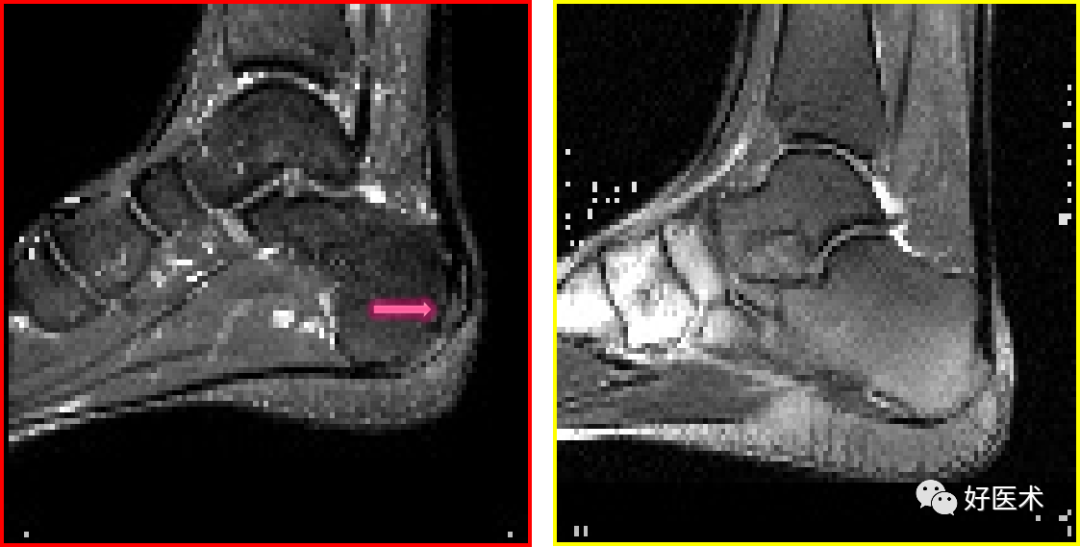

足底腱膜炎(跖腱膜炎)

正常足底腱膜

足底腱膜炎MRI表现

足底腱膜炎:注意跟骨内侧结节的局限性水肿